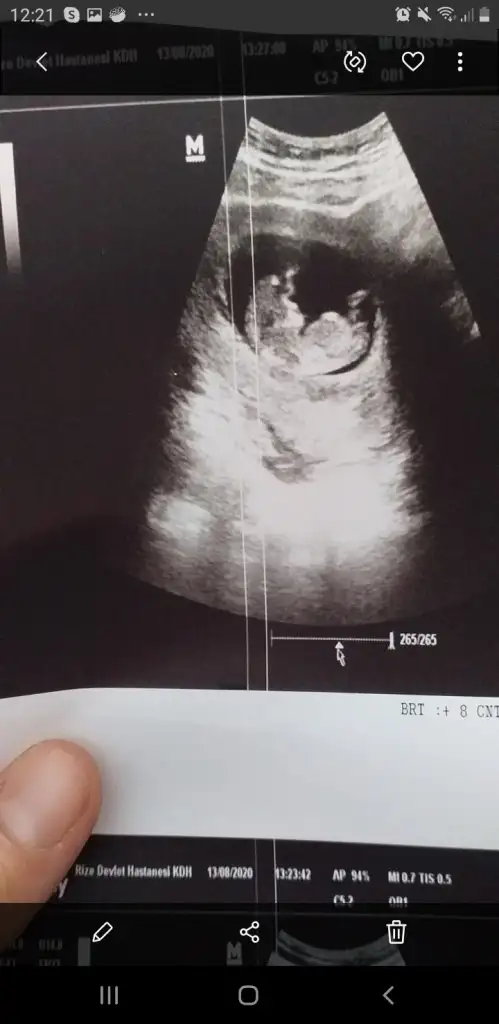

• Screenshot_20200824-122159_Gallery.webp

Screenshot_20200824-122159_Gallery.webp

17,4 KB · Görüntüleme: 114